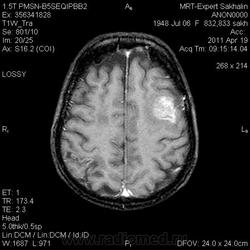

склоняюсь к кровизлиянию в левой теменной долей, начало перехода острой стадии в раннюю подострую( по периферии определяется повышение МРС по Т1 ВИ -метгемоглобин). Справа -старые кортикальные постишемческие глиозно-атрофические изменения. Контрастируется , вероятно за счет формирования участков ангионеогенза.

А мне кажентся больше за опухоль. Может быть сосудистая мальформация. Клинико-анамнестические данные есть?

Это демиелинизирующий процесс, острая стадия, причем с геморрагическим пропитыванием в центре пораженных участков. В принципе, соответствует тяжелому рассеяному склерозу, хотя может быть и геморрагическая форма ОДЭМ. Также могут быть мозговые проявления системного васкулита: надо знать анамнез.

На фоне ДЭП изменений МР-картина ОНМК по ишемическому типу в бассейне ЛСМА с участками геморрагического пропитывания. Аналогичный участок но в более поздней фазе в задних конвнкситальных отделах правой теменной доли.

О.С., я согласен, что контрастирование нехарактерно для ОНМК, ведь в подострую стадию инфаркта наблюдается, как правило, гиральный тип усиления. Плюс, на ОНМК непохоже то, что поражено почти только белое вещество, а кора интактна. И потом, при такой локализации инфаркта обязательно должна быть яркая клиника, и уж никак не только "головная боль".

Что касается снимочков мне кажется что зона патологического сигнала в левой гемисфере можно расценить как подострую стадию ОНМК с геморрагическим пропитыванием, справа как последствия ОНМК. При чем множественные очаги скорей всего как проявление ХМНК. И обязательно рекомендовать контрольное МРТ в динамике . Если это действительно ОНМК на фоне лечения отек уйдет и будет формированиться зона кистозно-глиозных изменений, а если отек будет нарастать значит надо думать о объемном процессе.

ОНМК по геморрагическому типу, почти классика.